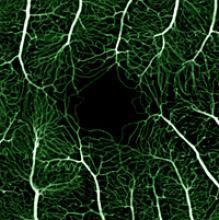

The retina viewed by phase variance-OCT.

Phase-variance OCT (top) can reveal blood vessels over the retina (yellow and red) and underneath it in a layer of tissue called the choriocapillaris (green). In this person with AMD, it also reveals areas of choriocapillaris loss (blue arrowheads). This level of detail isn’t seen by standard fluorescein angiography (bottom). Republished from Kim et al., PNAS.

“With phase-variance OCT, instead of acquiring each slice once, we acquire every slice three times in a row, and then we align them and ask what’s different,” Werner said. When there is motion between the three slices—for example, the flow of blood through veins and arteries—it creates contrast and enhances the composite image, he said.

In an NEI-funded study, Werner and colleagues used phase-variance OCT to examine the eyes of two volunteers in their 60s. One had no history of eye disease and the other had a type of advanced AMD called geographic atrophy. The researchers were able to see retinal vessels, as well as small vessels in a layer of tissue underneath the retina called the choriocapillaris.

In the person with AMD, they detected a loss of these small choroidal vessels, which typically aren’t visible with fluorescein angiography or other standard methods.